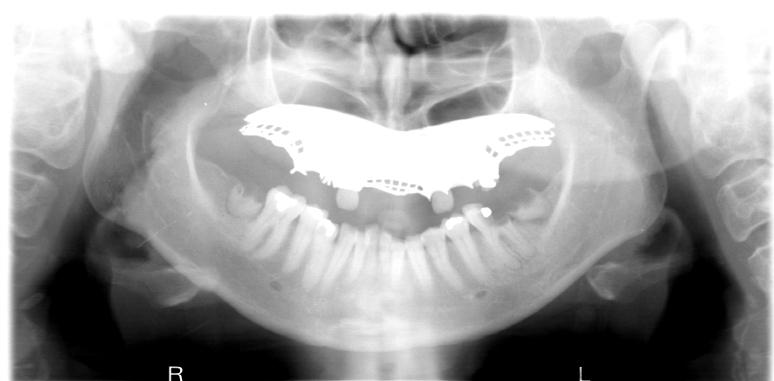

7

Q

What is wrong with this image?

A

removable prosthodontic device